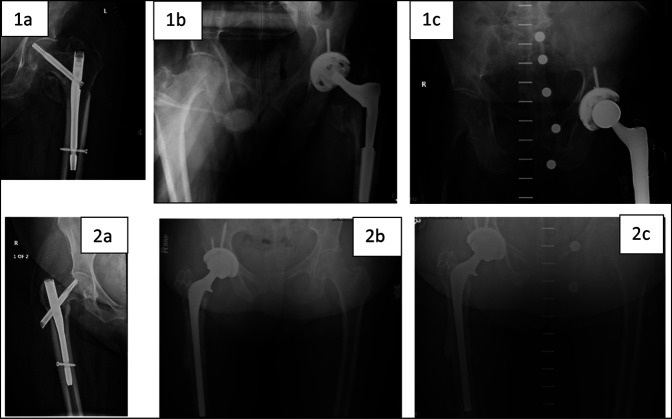

Results: A diaphyseal-engaging revision stem was used in 13 cases, with metaphyseal press-fit stems and cemented stems each used in 3 cases. Two patients (one diaphyseal stem, one cemented stem) sustained intraoperative greater trochanteric fractures. No postoperative fractures were found. Four emergency department visits (21%) and one unplanned readmission (5%) were reported within 30 days, with 1 emergency department visit (5%) and two readmissions (11%) within 90 days. Stratified by stem type, we observed no notable difference in length of stay or procedure length.

Discussion: This is the first study to investigate conversion to THA from short IMN. Overall, there were two intraoperative fractures, but no distal fractures or revisions. Although the distal interlock screw was commonly bypassed with a revision-type diaphyseal stem, this was not universal. Further research is needed to determine if primary arthroplasty stem designs can be used in this setting.